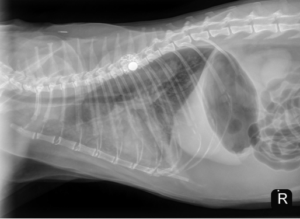

Unfortunately, the patient represented to the PVESC ER the day after discharge, for dyspnea, drooling, and frothing as well as an expiratory wheeze. On presentation he was given a 2 mg/kg dose of furosemide IM as well as butorphanol and alfaxalone for sedation to complete initial diagnostics. Thoracic radiographs on intake showed a mild cardiomegaly, moderate patchy interstitial pattern, and mild pleural fluid (see below). He was continued on 2 mg/kg furosemide IV (received two total doses approximately 4 – 6 hours apart). Later that day, an echocardiogram was performed which showed mild to moderate diffuse left ventricular concentric hypertrophy and only high normal left atrial size. The size of the left atrium was unexpected for the degree of pulmonary edema present on radiographs. At the time it was suspected that the patient likely experienced congestive heart failure secondary to fluid intolerance with underlying cardiomyopathy. Naturally occurring congestive heart failure (meaning congestive heart failure secondary to natural progression of feline cardiomyopathy) was considered less likely given the normal to minimally enlarged left atrial size (however, it could not be fully ruled out). The patient was discharged in the evening with oral medical management (furosemide, clopidogrel, and spironolactone) as he experienced significant stress in hospital and his respiratory rate and effort had improved significantly since presentation without the need for continued oxygen supplementation.